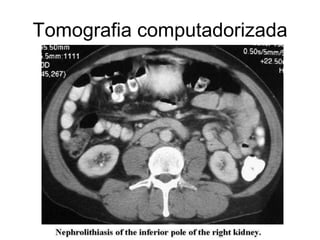

Tomografia computadorizada